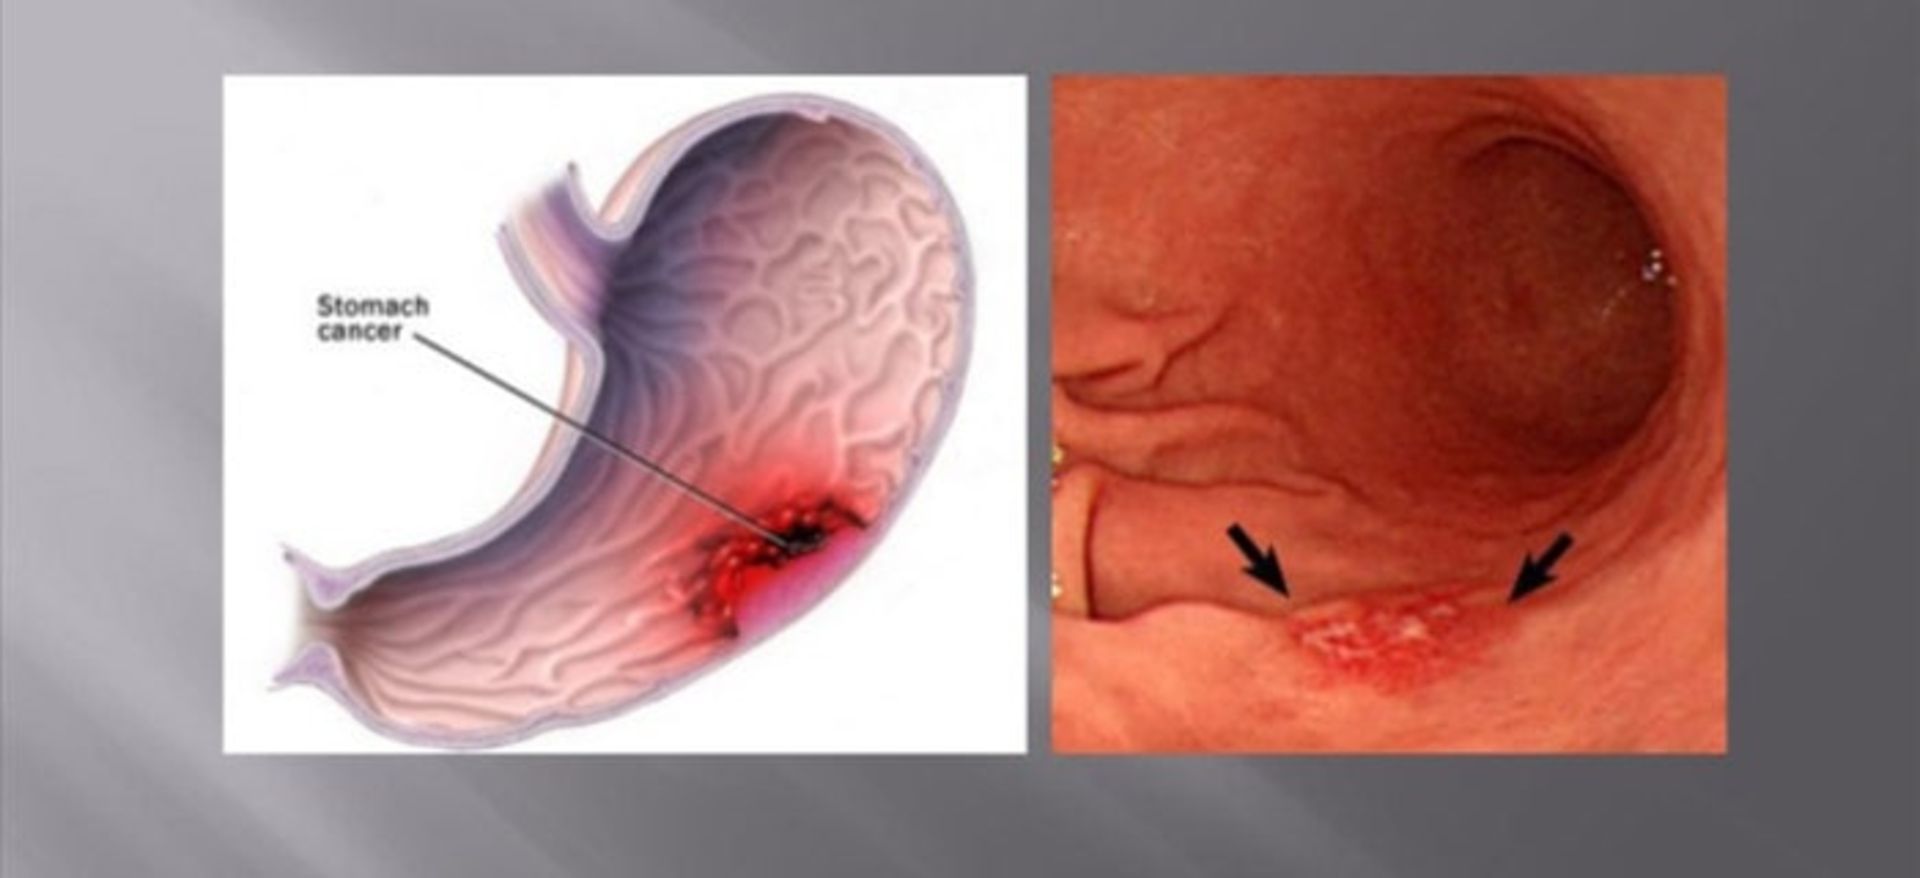

پیشروی سرطان معده

بهطور معمول سرطان معده بهآهستگی و در طول چندین سال توسعه پیدا میکند. قبل از پیدایش یک سرطان واقعی، اغلب یک سری تغییرات پیشسرطانی در لایهی مخاط معده اتفاق میافتد. این تغییرات اولیه بهندرت موجب ایجاد علایمی میشوند و بنابراین اغلب تشخیص داده نمیشوند. سرطانهایی که در بخشهای مختلف معده آغاز میشوند، ممکن است علایم متفاوتی را ایجاد کنند و دارای پیامدهای مختلفی باشند.

انواع سرطانهای معده

آدنوکارسینوم: درحدود ۹۵-۹۰درصد از سرطانهای معده از نوع آدنوکارسینوم هستند. این نوع سرطان اغلب از داخلیترین لایهی معده یعنی لایهی مخاط آغاز میشود.

آندوسکوپی فوقانی: آندوسکوپی فوقانی یا EGD آزمایش اصلی تشخیص سرطان معده است. در این آزمایش، پزشک یک آندوسکوپ را که یک لولهی نازک دارای منبع نور و یک دوربین ویدئویی کوچک است، از راه گلو وارد معدهی فرد بیمار میکند. با این کار پزشک میتواند پوشش مری، معده و بخش ابتدایی رودهی کوچک را ببیند. اگر مناطق غیرطبیعی مشاهده شوند، با استفاده از ابزاری که به آندوسکوپ متصل است، نمونهبرداری انجام میشود. این نمونهها به آزمایشگاه فرستاده میشوند و با استفاده از میکروسکوپ مشخص میشود که آیا سلولهای سرطانی وجود دارند یا خیر. با استفاده از آندوسکوپ، سرطان معده میتواند شبیه یک تودهی برآمده یا قارچمانند، یا مناطق ضخیم شده، مسطح و پراکنده از مخاط دیده شود که با عنوان لینیت پلاستیکا شناخته میشوند. سندرم سرطان ارثی منتشرهی معده، اغلب ازطریق آندوسکوپی قابل رویت نیست.